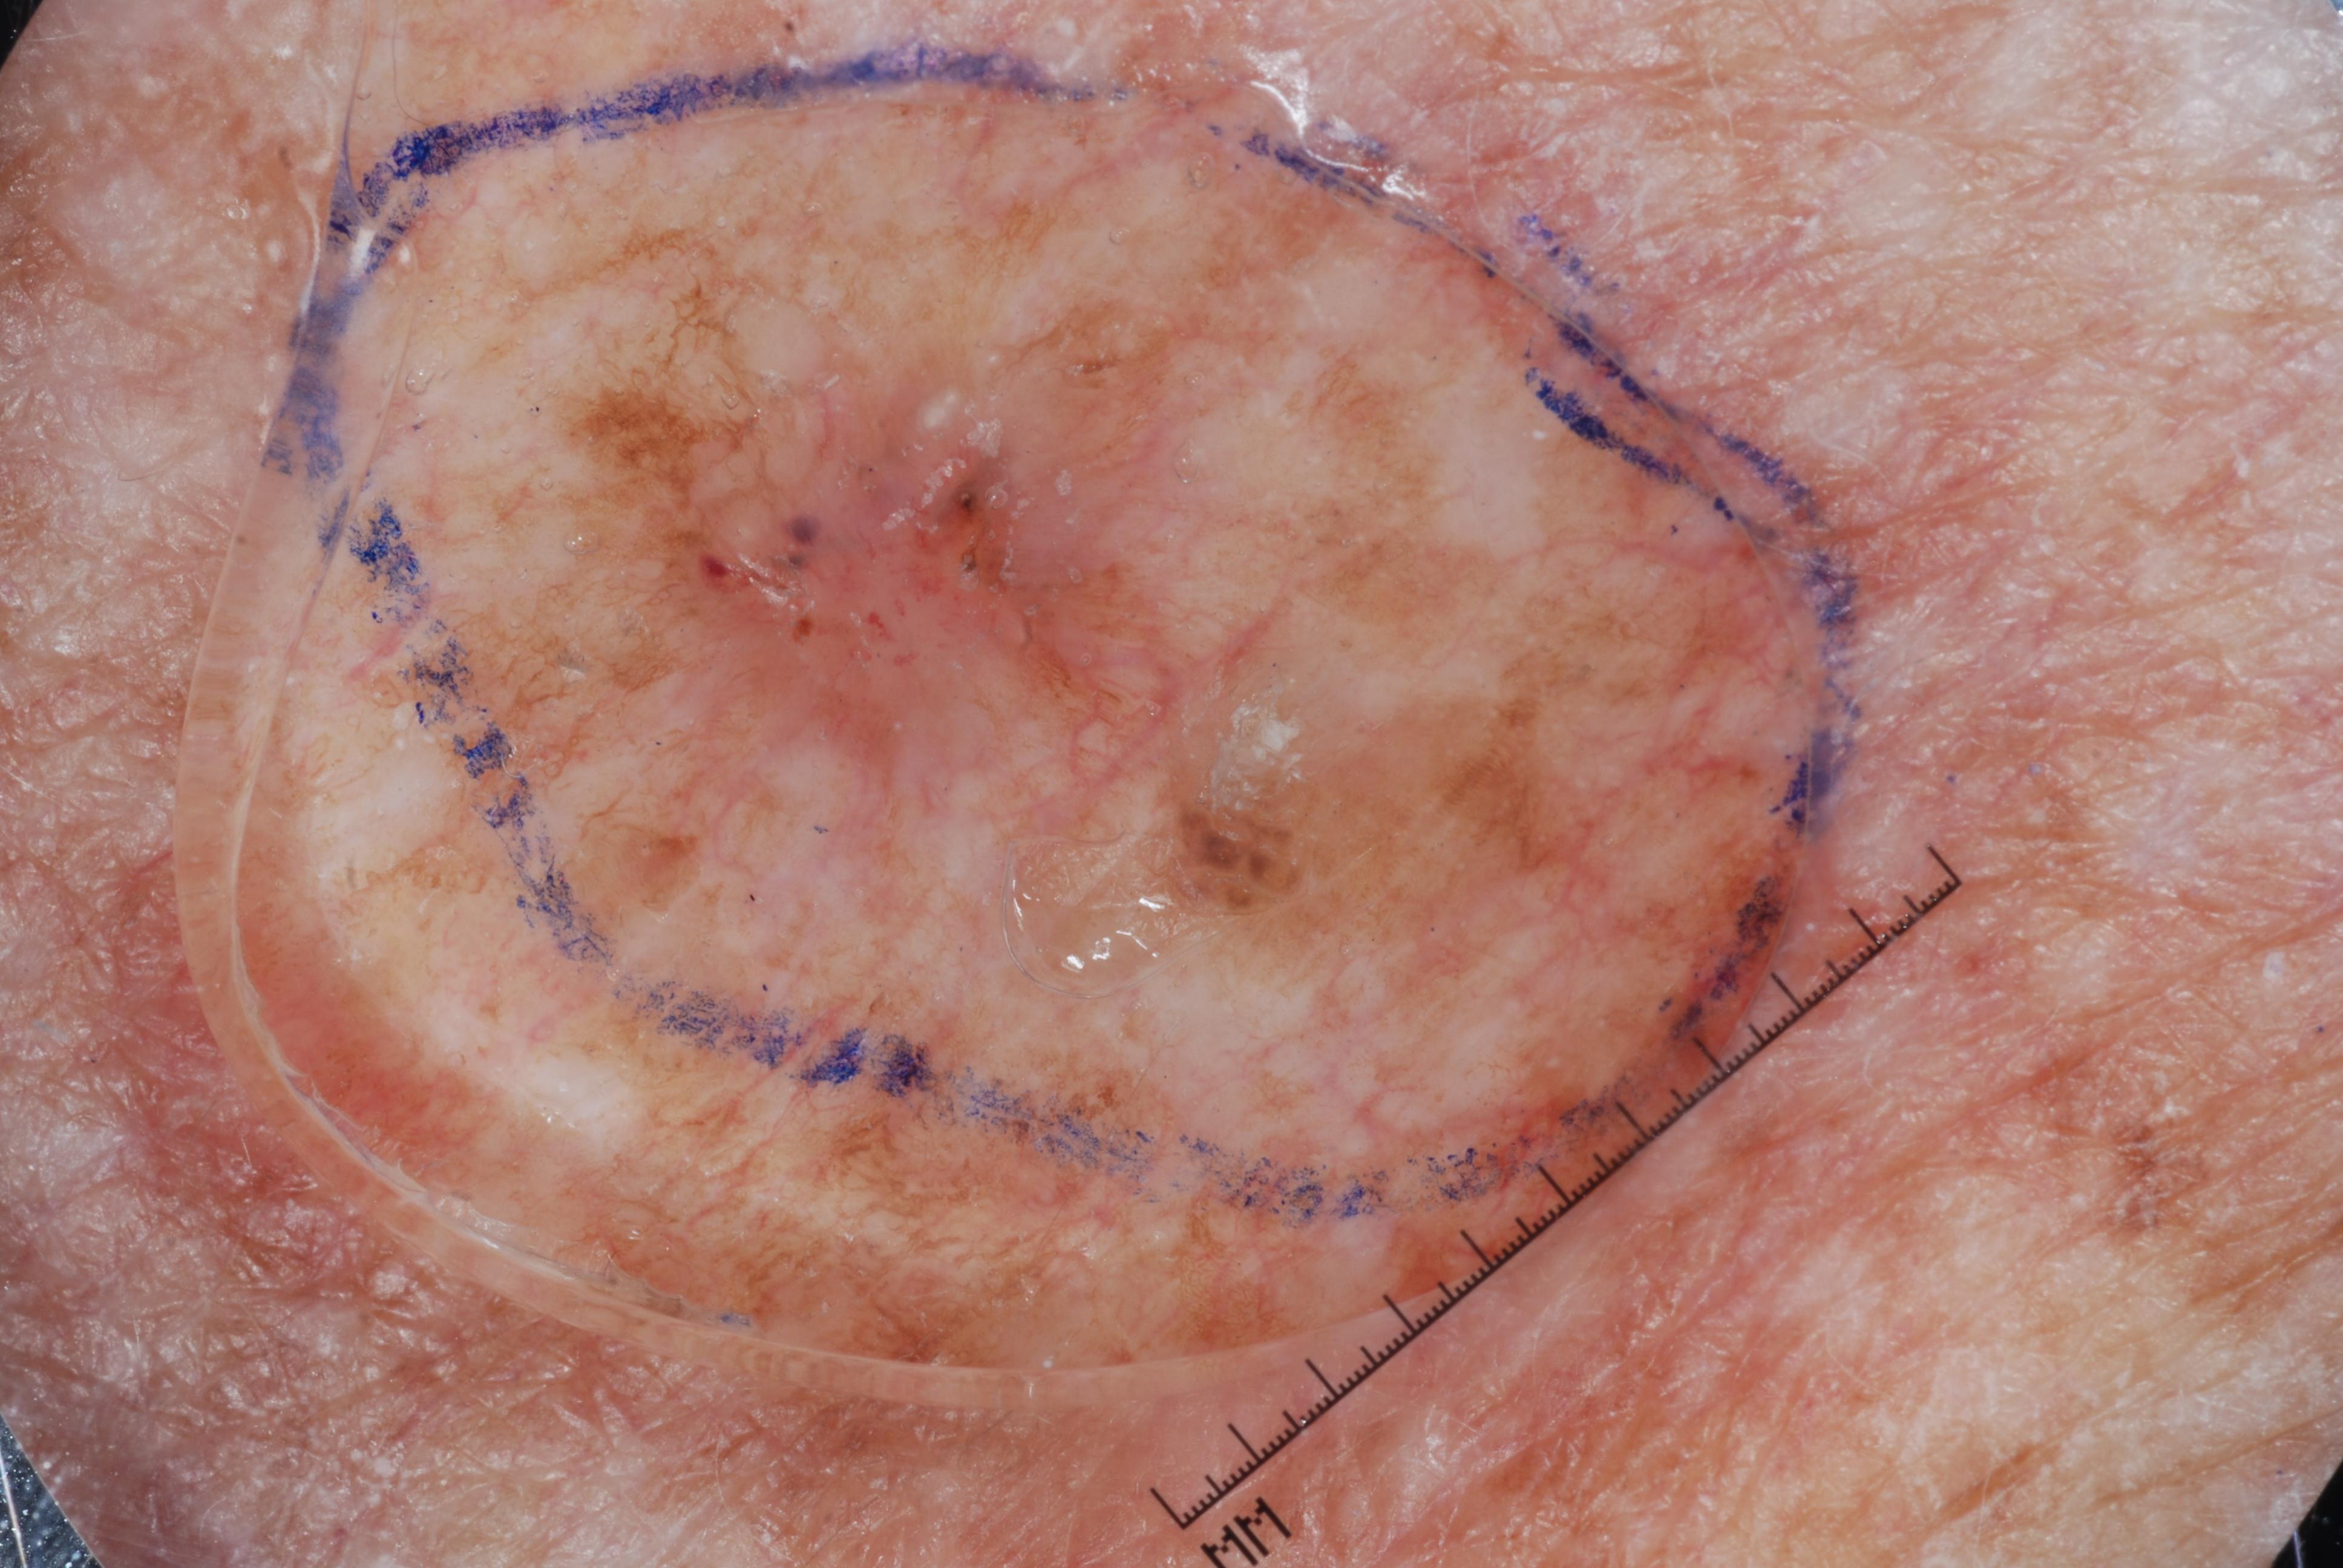

{

"age_approx": 80,

"anatom_site_general": "posterior torso",

"concomitant_biopsy": true,

"dermoscopic_type": "contact non-polarized",

"diagnosis_1": "Malignant",

"diagnosis_2": "Malignant adnexal epithelial proliferations - Follicular",

"diagnosis_3": "Basal cell carcinoma",

"diagnosis_confirm_type": "histopathology",

"image_type": "dermoscopic",

"lesion_id": "IL_6461577",

"melanocytic": false,

"sex": "male"

}